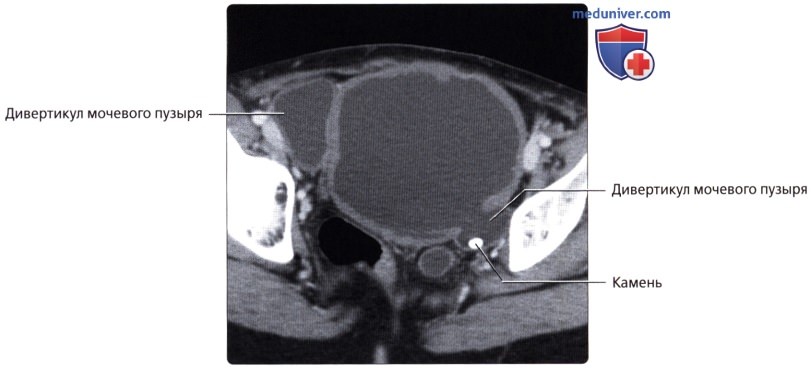

Изображения КТ конкрементов мочевого пузыря